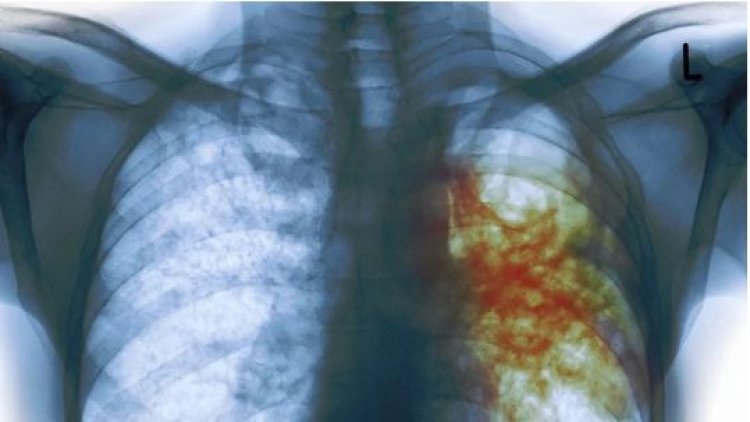

Imyumvire, kutagira amakuru: zimwe mu mpamvu zituma igituntu kidacika.

Mu Rwanda haracyagaragara umubare munini w’abarwayi b’igituntu,akenshi biterwa no kutamenya amakuru kur’ iyi ndwara ndetse ni imyumvire ya bamwe nubwo bamwe mubakirwaye bavuga ko bafata imiti neza kandi byagiriye akamaro. Ni mugihe ikigo cyita ku buzima kivuga ko mu rwego rwo gufatanya n’isi kurandura iyi ndwara, begereje abarwayi service zo kuyivurira ku bigo nderabuzima kandi ku buntu.

Abatuye isi bihaye intego y’uko kugera mu 2035 bazaba babashije kurandura burundu indwara y’igituntu. Nubwo bimeze bityo ariko, hirya no hino haracyagaragara umubare munini w’abandura iyi ndwara ndetse n’abo ihitana.

Nubwo hagiye hashyirwaho ingamba zitandukanye zirimo gupima no gutanga ubuvuzi bw’indwara y’igituntu ku buntu, ntibyabujije ko buri mwaka mu Rwanda na ho hakigaragara umubare munini w’abacyandura.

Ibi ahanini biterwa n’imyumvire ikiri hasi ndetse bamwe bakaba bakiyitiranya n’amarozi, nk’uko bivugwa na Maiboni M.Louise; ushinzwe gukurikirana abarwayi b’igituntu ku kigo nderabuzima cya Kabusunzu.

Igituntu ni indwara iza mu 10 za mbere zica, kur’ubu imibare igaragazwa ni ishami ry’umuryango w’abibumbye ryita ku buzima[OMS] igaragaza ko mu bantu 100 000, 56 muribo baba barwaye igituntu. Ibi bikaba aribyo bishingirwaho ko isi yose yiha intego ko muri 2035 nta gituntu cyaba ki kiriho